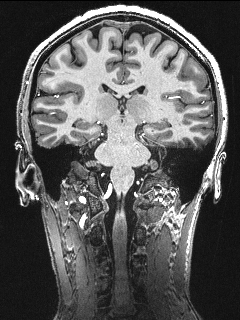

High-Resolution Structural Imaging

In addition to the modalities above, we also acquire high-resolution T1 and T2w modalities including MPRAGE, MP2RAGE, SPACE, TSE, FLAIR and MT images for brain morphometrics, hippocampal subfields, and locus coeruleus/circle of willis imaging.

Imaging parameters

- MPRAGE: 0.75 mm isotropic resolution, acquisition time = 6 min

- MP2RAGE: 0.55 mm isotropic resolution, acquisition time = 13 min

- SPACE: 0.6 mm isotropic resolution, acquisition time = 10 min

- TSE: 0.375x0.375x1.5 mm3 resolution, acquisition time = 4 min for hippocampus segmentation, 8 min for whole brain

- FLAIR: 0.75x0.75x1.5 mm3 resolution, acquisition time =11.5 min

- MT: 0.4×0.4×0.5 mm3 resolution, acquisition time = 4:38 min